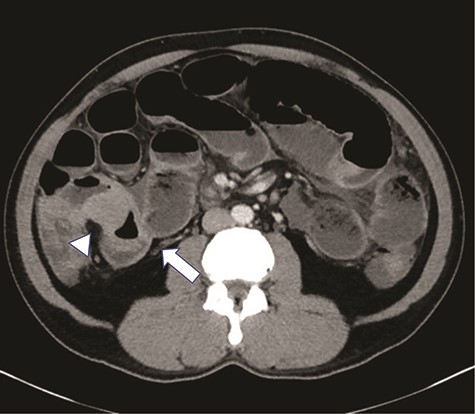

A 47-year-old male presented to the Emergency Department with abdominal pain, nausea, emesis and diarrhea for four days. His last bowel movement was the day prior and he was continuing to pass flatus. On physical examination, his abdomen was soft and nondistended, with tenderness in the epigastrium and left lower quadrant. His vital signs and laboratory values were within normal limits. Computerized topography (CT) scan showed a high-grade SBO with a transition point within distal ileum with asymmetric irregular bowel wall thickening, which was suggestive of a mass (Fig. 1). A moderate amount of ascites was also noted, as well as an appendicolith within the appendix, mildly thickened to 8 mm without any other sign of inflammation (Fig. 2). The patient was admitted to the hospital for initial conservative management, and a cancer work up was initiated for a primary SBO. CT of the chest showed no distant metastases. Tumor markers (carbohydrate antigen 19–9, carcinoembryonic antigen and alpha-fetoprotein) were all within normal limits. Over the next three days, the patient regained bowel function and his pain improved. He opted for outpatient colonoscopy and surgery and was discharged home. Two days later, the patient represented to the ED with abdominal pain, distention and emesis. He had a normal white blood cell count with neutrophilia and lactic acidosis of 3.1. A repeat CT scan of the abdomen and pelvis showed essentially unchanged findings from the prior study. He then was taken to the operating room for exploratory laparotomy. A firm mass was noted 20 cm proximal to the terminal ileum with a mass lesion and an abnormal, firm appendix. We performed a small bowel resection and appendectomy. The patient was subsequently referred to the hematology/oncology department for further treatment. He underwent a bone marrow biopsy which was negative for evidence of leukemia and subsequently began treatment with induction chemotherapy.

There is an appendicolith noted within the proximal appendix which is mildly thickened measuring up to 8 mm (arrowhead).